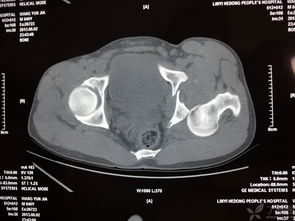

髖臼骨折,恥骨骨折,經(jīng)檢查無(wú)需住院,2回答者:lianghuanjie